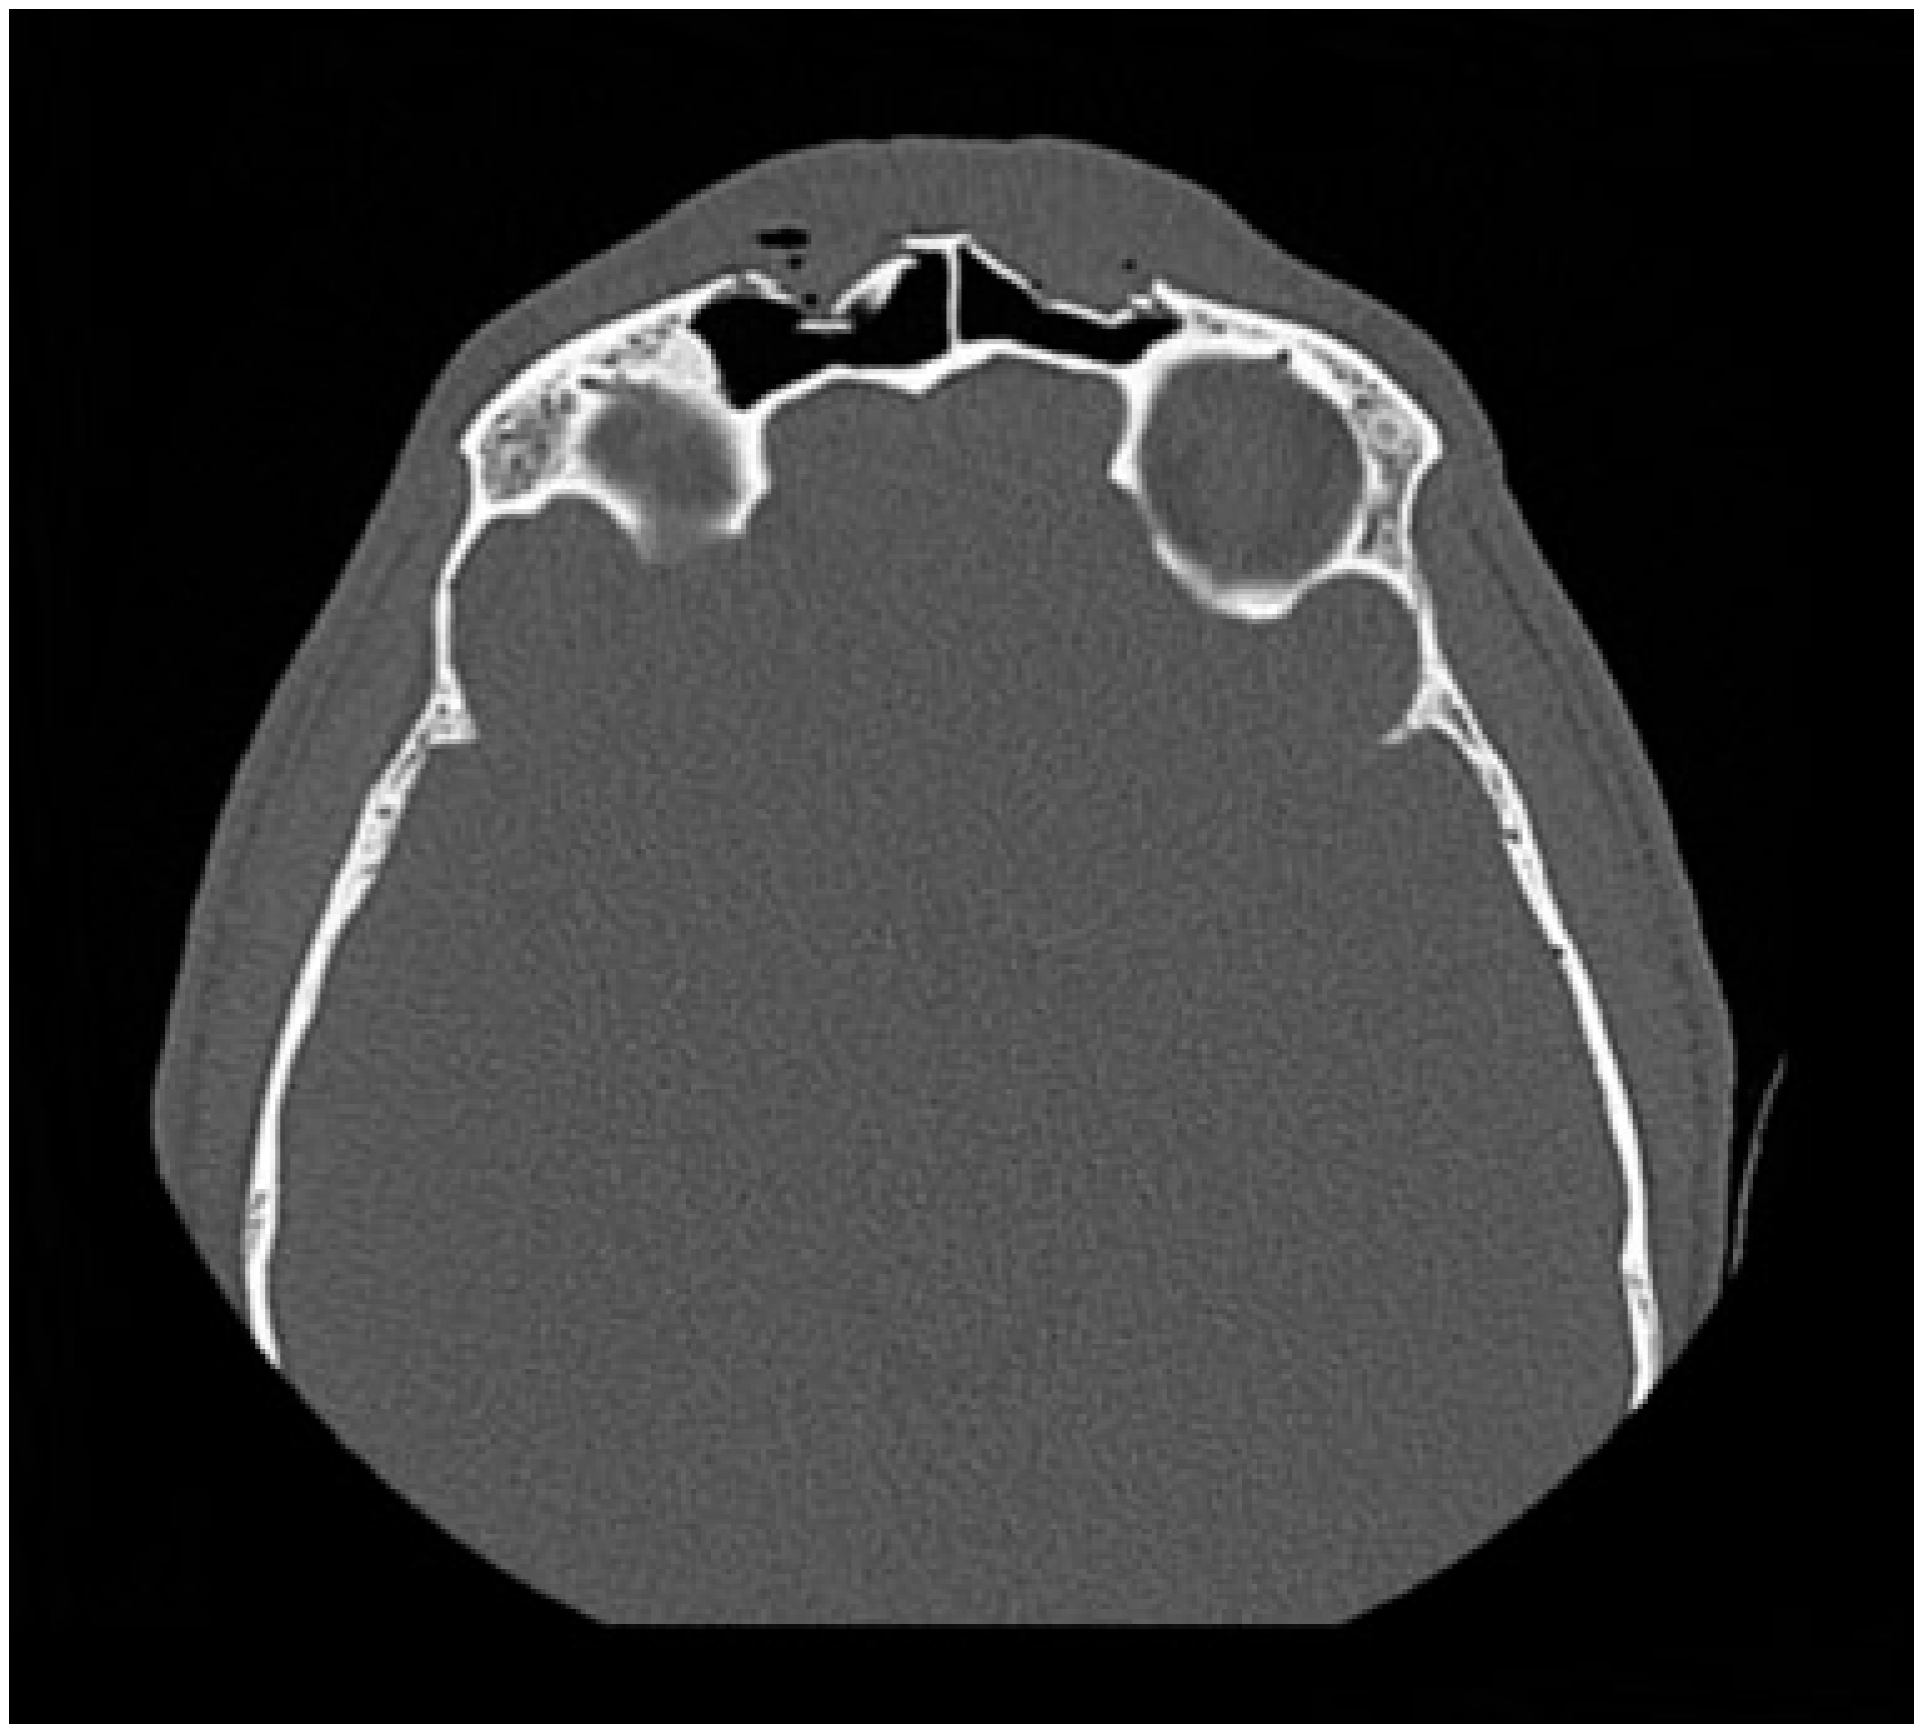

Fractures isolated to the anterior table account for 18–27% of frontal sinus fractures.[3,5,16] The indication for repair has mainly focused on correcting a cosmetic deformity. Without injury to the frontal sinus outflow tract or posterior table, many series have reported on the safety of observation of isolated anterior table fractures.[1,3,4,17,18] The degree of displacement necessitating repair is controversial. The degree of displacement seen on CT imaging may not correlate with the either the visualized or palpated deformity due to overlying edematous soft tissue. It is also difficult to predict the degree of resultant deformity after the acute swelling subsides (Figure 2). Furthermore, physician and patient expectations vary regarding the definition of an “acceptable” forehead contour. With observation, bony remodeling and scarring over an intact periosteum may subsequently hide any cosmetic deformity, especially in pediatric patients [19].

Figure 2.

CT in the axial plane demonstrating a comminuted, displaced bilateral fracture of the anterior table of the frontal sinus fracture. In the acute setting, significant soft tissue edema may obscure a palpable deformity.